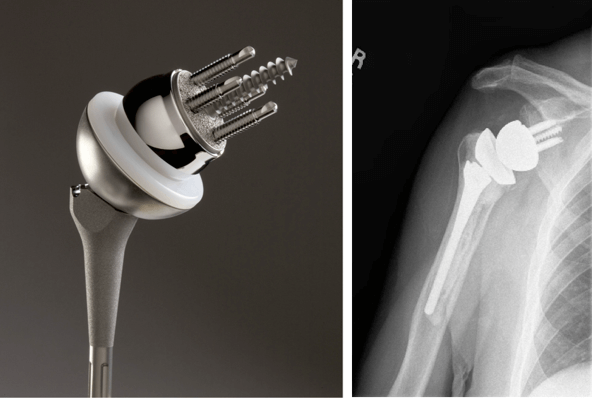

Имплантаты на ножке по своему строению могут быть анатомическими и обратными. Анатомический состоит из трех частей: головка, ножка и впадина. Назван так, поскольку полностью повторяет структуру человеческого плеча и по биомеханике, и по форме.

Установка такого протеза возможна только в том случае, если вращательная манжета не повреждена. При замене используется продукция таких мировых производителей как DePuy, Zimmer, Smith&Nephew, Biomet, Aesculap — B. Braun.

Обратный или реверсивный используется, когда вращательная манжета не функционирует и нарушена стабильность. Тогда головка крепится к суставной впадине (гленоидальному компоненту), а вогнутый имплантат впадины на ножке фиксируется на плечевой кости.

Для однополюсного эндопротезирования используются гемипротезы, то есть заменяющие только одну часть сустава. По способу установки делятся на поверхностные и штыревые (внедряются в кость).

Ревизионное эндопротезирование в случае обширного поражения тканей, замены эндопротеза или сильного разрушения кости требует специального имплантата, который частично компенсировал бы функциональную недостаточность мышц. Например, Delta XTEND производства компании DePuy. Центр ротации у него смещен вниз и кнаружи, что увеличивает диапазон движений, сохраняя при этом стабильность сустава.